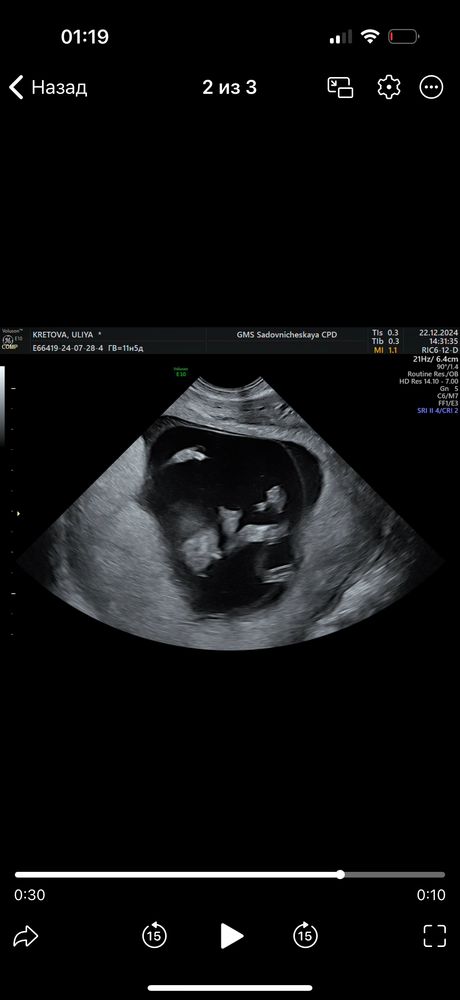

Юлия Флинк, тогда это скорее всего пацан, если торчит между ног. у меня аналогично также было на узи 14,5(можете у меня в дневнике посмотреть). узистка заверила меня, что это уже 100% . но некоторые на бб я видела писали, что пол окончательно формируется после 15-16 недель. так что будем ждать 2 скрининг)

19.01.2025